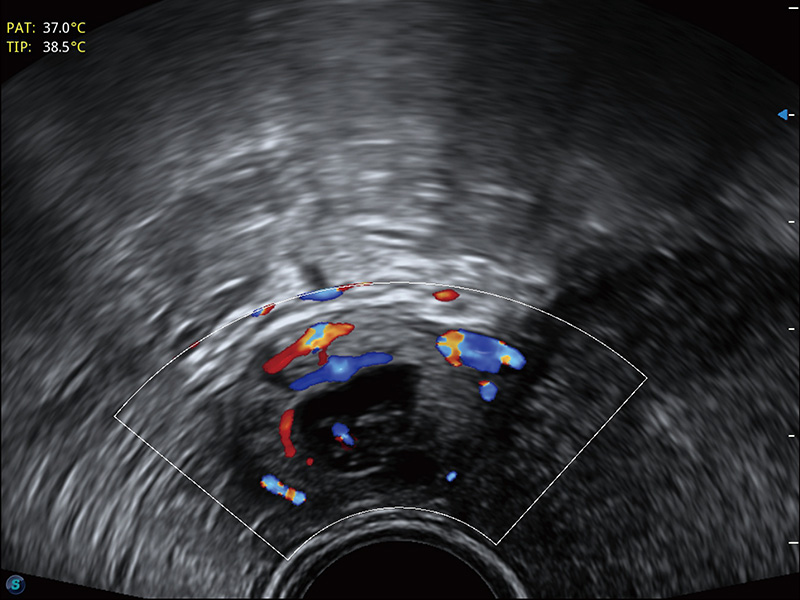

“生育问题”即关系民族复兴,也关系亿万家庭的幸福。随着婚育年龄推迟、社会压力增加等因素,越来越多人群也面临着“生不出、生不好”的问题。辅助生殖作为治疗不孕不育最有效的方法之一,也逐渐成为育儿新希望。而超声检查能为生殖需求人群的初诊评估提供宝贵的信息。 P20 Elite是db真人体育官网匠心打造的一款生殖应用型彩超。她继承db真人体育官网高端极光平台,突破性地将多款新型芯片及硬件模块进行整合,均衡了高端系统性能与小巧灵动机身。P20 Elite卓越的图像质量搭载专科探头,旨在为您提供全面的辅助生殖解决方案。

P20 Elite配备了丰富的生殖探头群和临床应用功能,在卵泡监测、穿刺取卵、胚胎移植、妊娠确认等领域,为生殖需求人群提供了新的临床机会,重新定义高端超声如何应用于生殖健康检查。

耦合剂加热器可将耦合剂维持在舒适的温度,体现患者关爱。